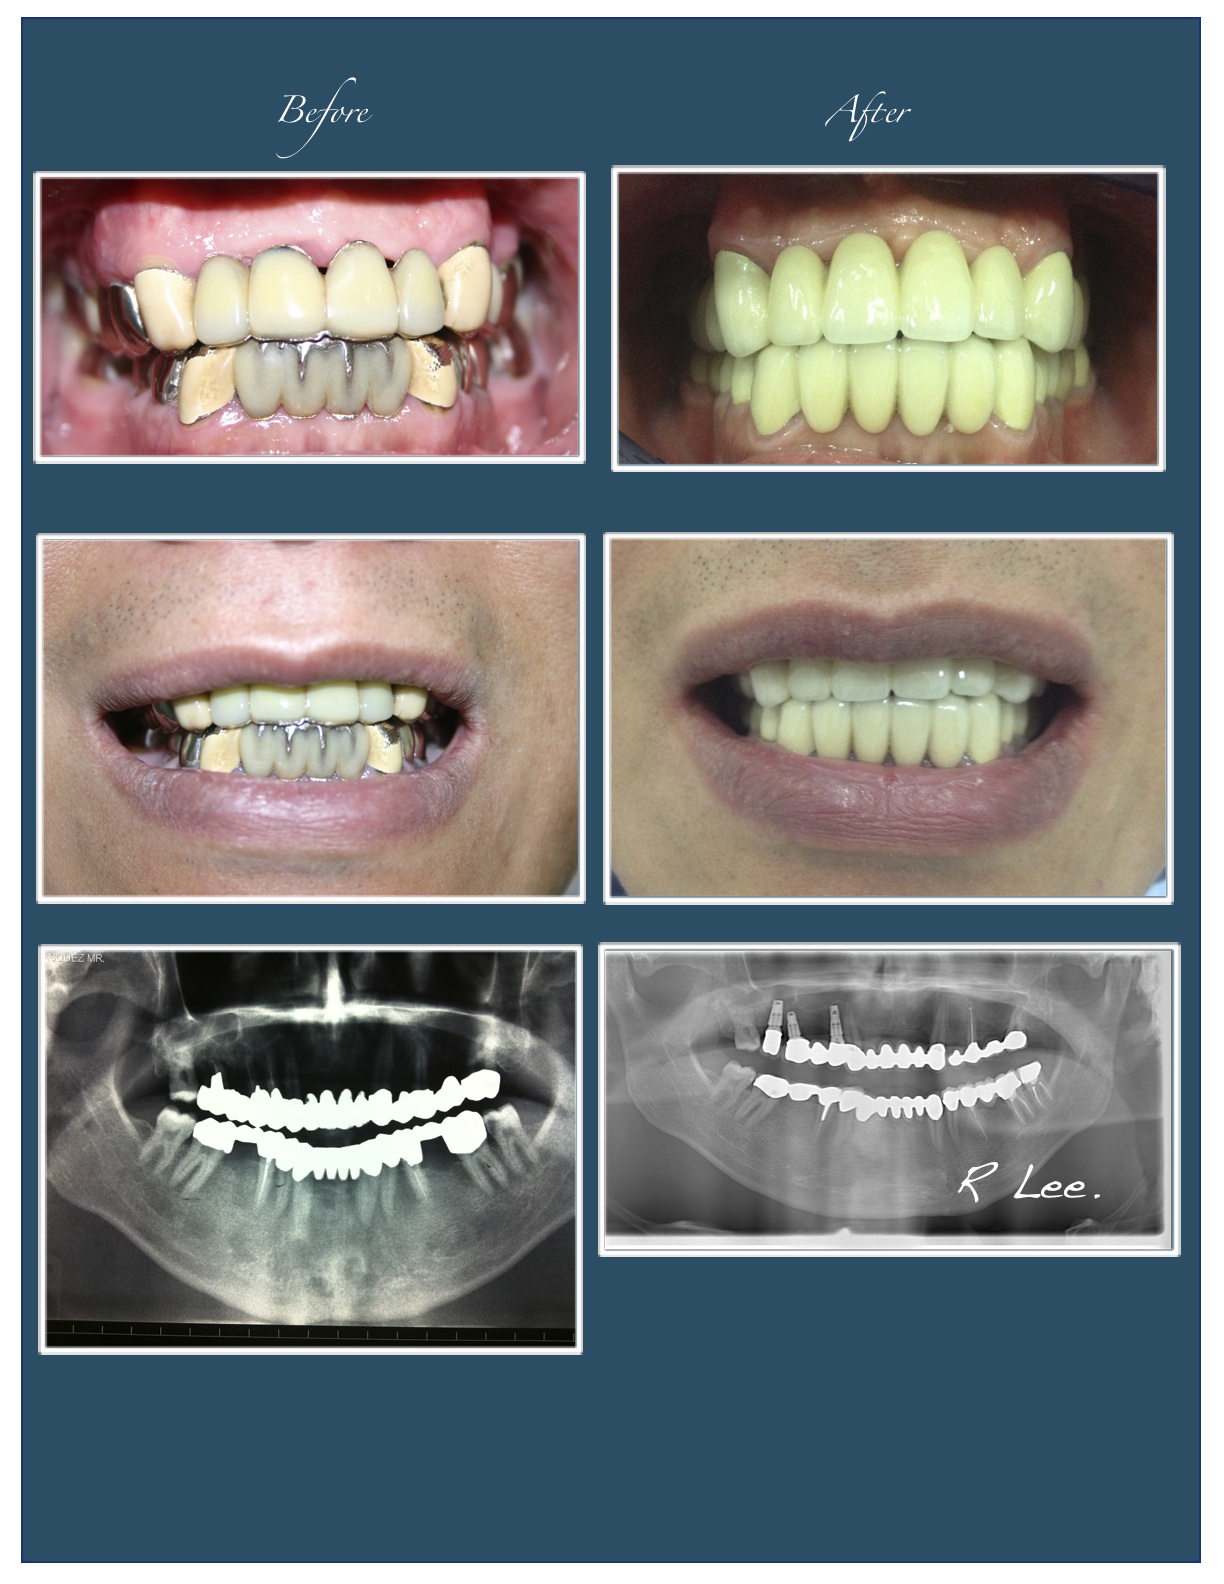

Dental Implant, Full mouth reconstruction

Full mouth reconstruction: Mr. GV